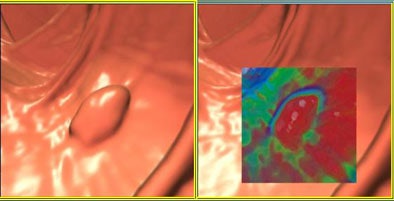

One possible way to reduce false positives and negatives in 3D is translucency rendering (TR) -- software that color maps minor differences in attenuation. Different colors (blue, green, red, and white) are assigned to areas of increasing attenuation, making it easier to distinguish the relatively homogeneous density of true polyps from more heterogeneous residual materials.

"3D translucency rendering is an accurate tool to easily differentiate true polyps from polypoid-like fecal residues during real-time 3D fly-through," he said. "However, unmarked fecal residues (FP calls) or opacified-coated true polyps (FN calls) may still be misinterpreted," necessitating the use of 2D confirmation in all cases. "So the purpose of the study was to evaluate the efficacy of translucency rendering for differentiating polyps from polyp-like residues," he said.

| Above, concentric circles and homogeneous interior of lesion depict the presence of a true polyp on translucency rendering software (Viatronix V3D Colon), shown with adjacent 2D correlations. Below, heterogeneous density of polypoid findings help identify residual fecal material. All images courtesy of Dr. Antonio Guerrisi. |